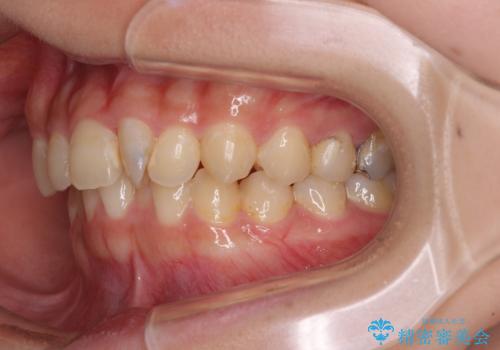

- 前歯のデコボコと深い咬み合わせを改善したいとのことで来院された患者様です。

奥歯の咬み合わせは上顎に対して下顎が後方位にあり、上顎前歯で下顎前歯が隠れるような典型的な過蓋咬合です。

補助装置を用いて上顎大臼歯を後方に移動させながら、ワイヤー装置で歯列を整えて深い咬み合わせを挙上することとしました。

下顎の装置が頻繁に脱落し、治療は難航しましたが、当初予定の2年間で無事に治療を終えることができました。